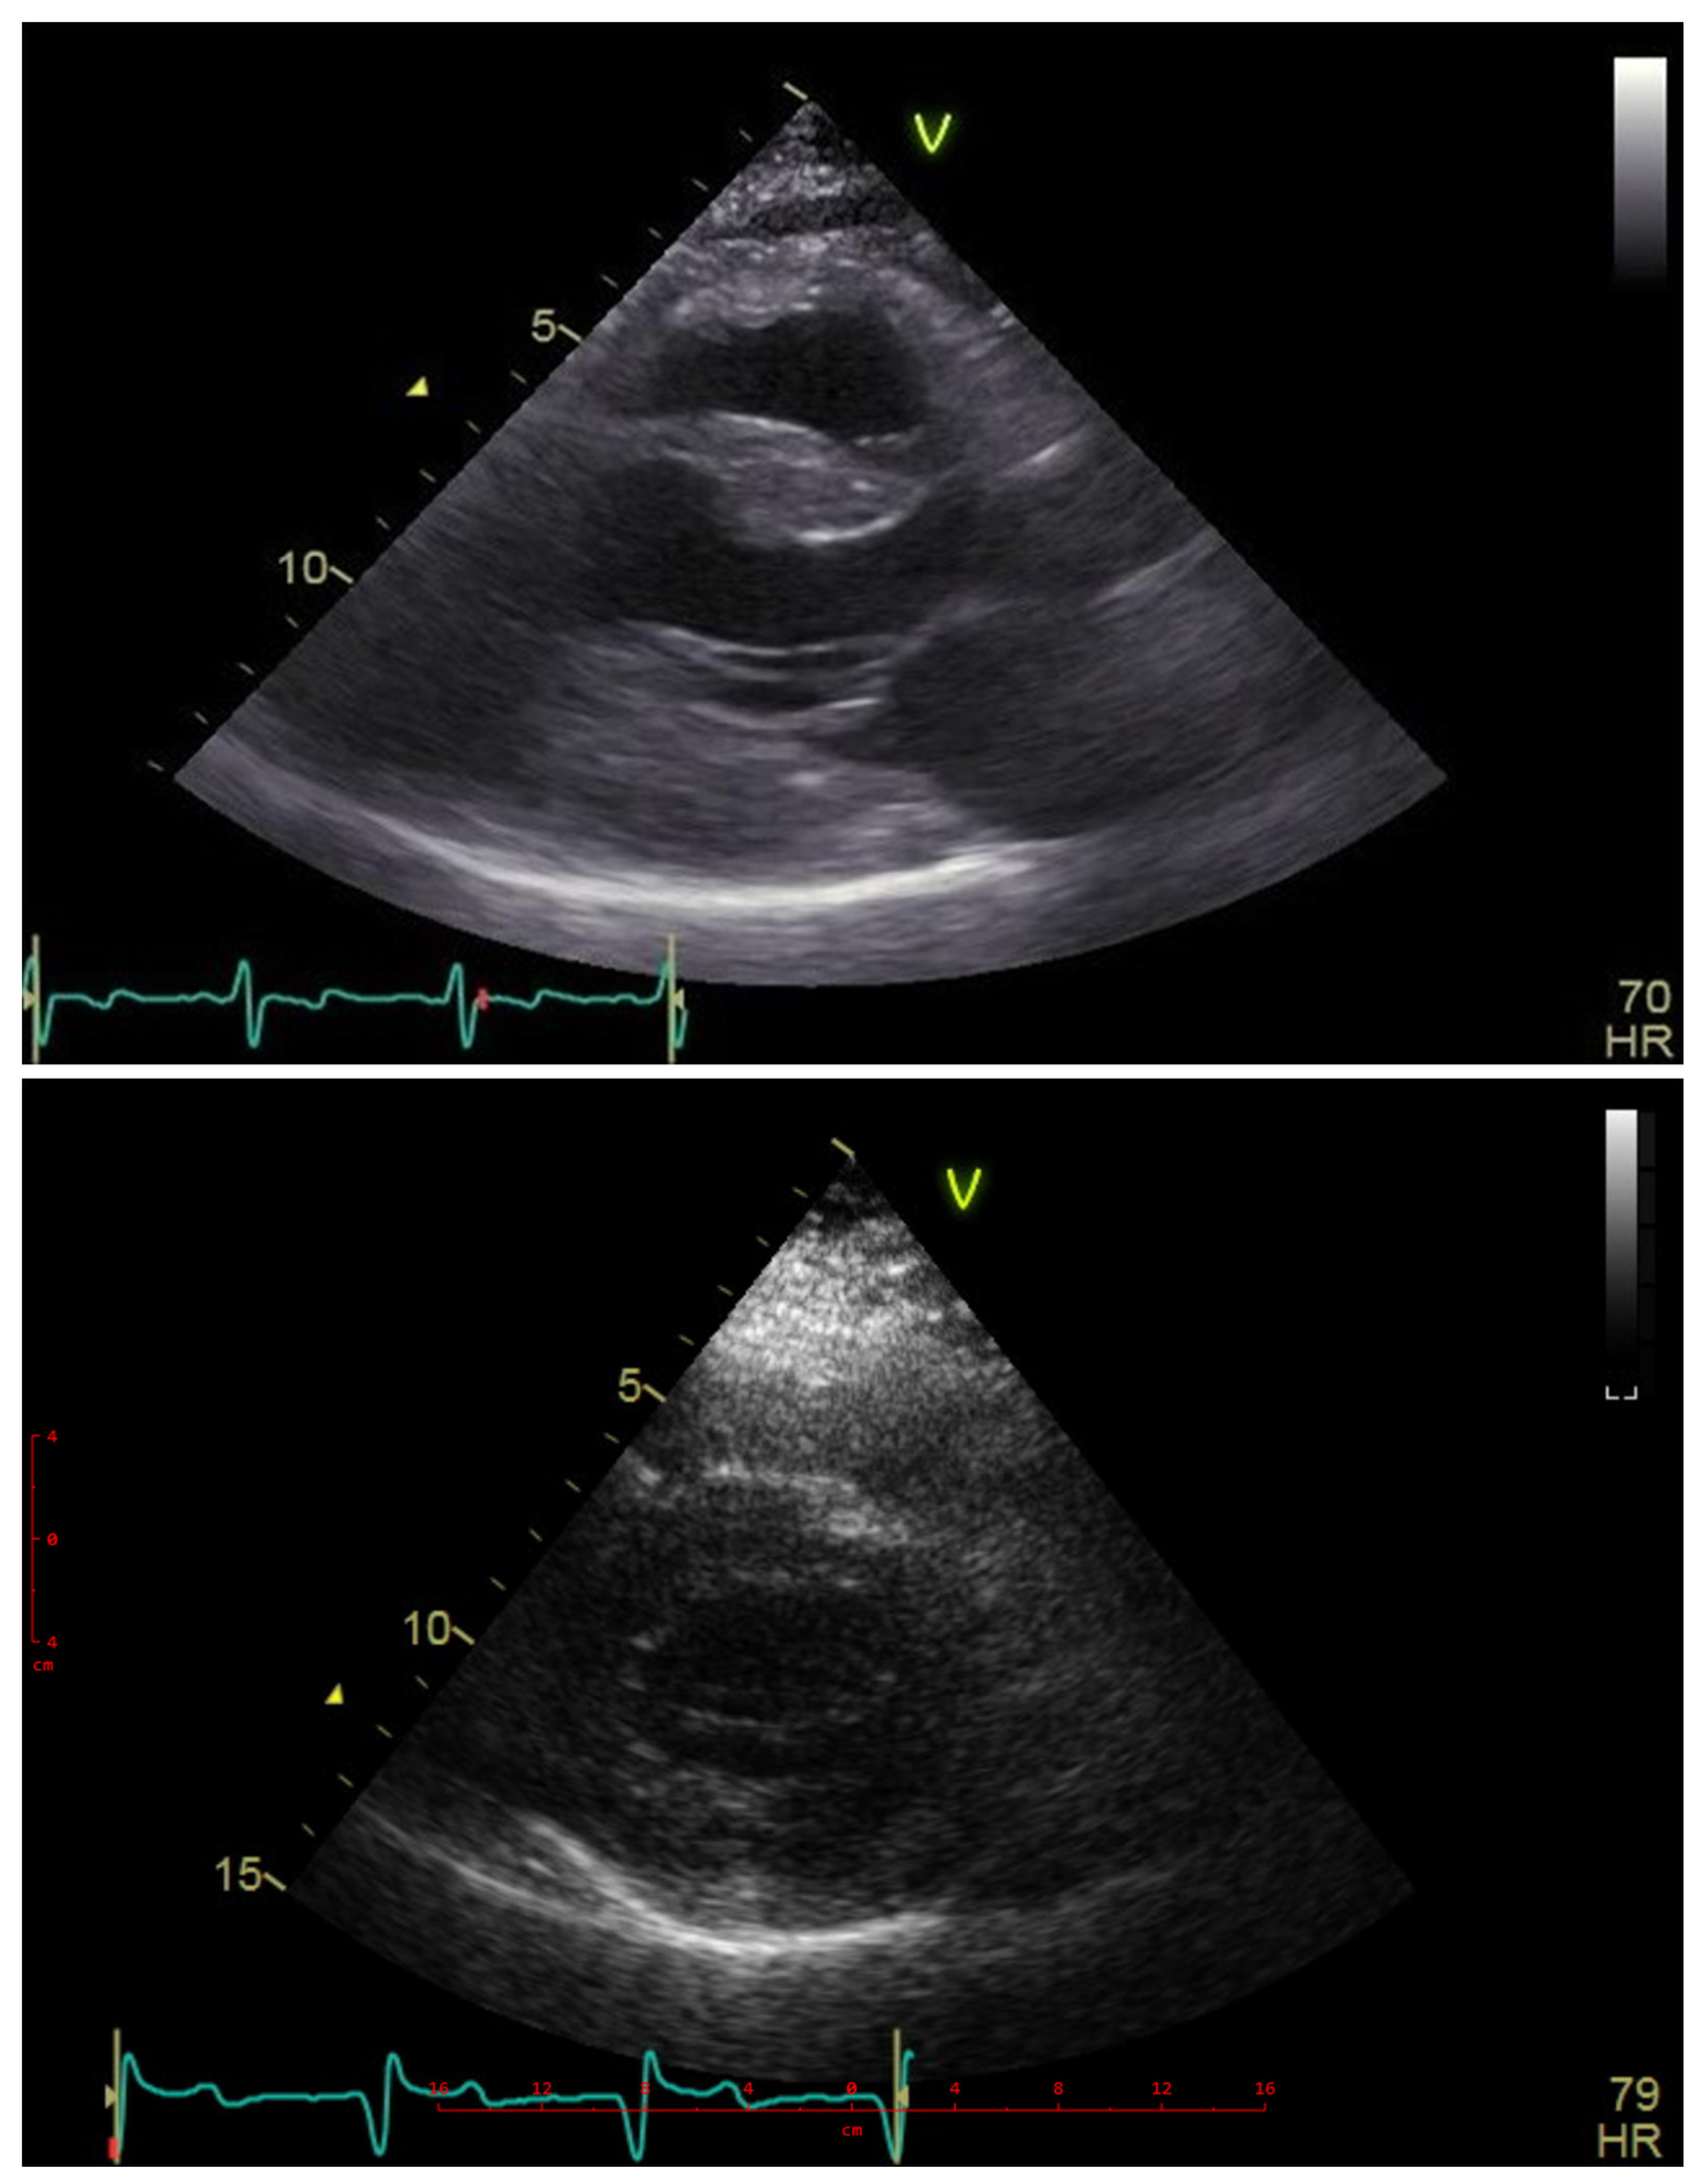

2. Case Description